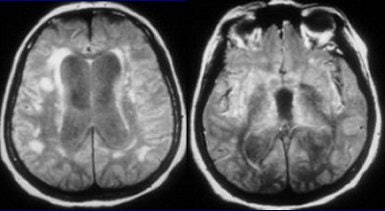

![]() |

| Seventy-eight-year-old female patient evaluated for suspected NPH. A and B, MRI FLAIR sequence (1 tesla, TR 11,000 msec, TE 140 msec, TI 2,600 msec) shows dilatation of the ventricles and sylvian fissures. C and D, FLAIR after 100% O2 for five minutes shows increased SI in the sulci and the posterior aspects of both sylvian fissures, allowing visualization of hypointense cysts (arrows) due to neurocysticerosis more anteriorly within the sylvian fissures. Note that there is no increase in the SI of the CSF within the ventricles. Braga FT, da Rocha AJ, Filho GH, Arikawa RK, Ribeiro IM, and Fonseca RB, "Intensity of CSF Depicted by Fluid-Attenuated Inversion Recovery Imaging," (AJNR, 24:1863-1868, October 2003). |